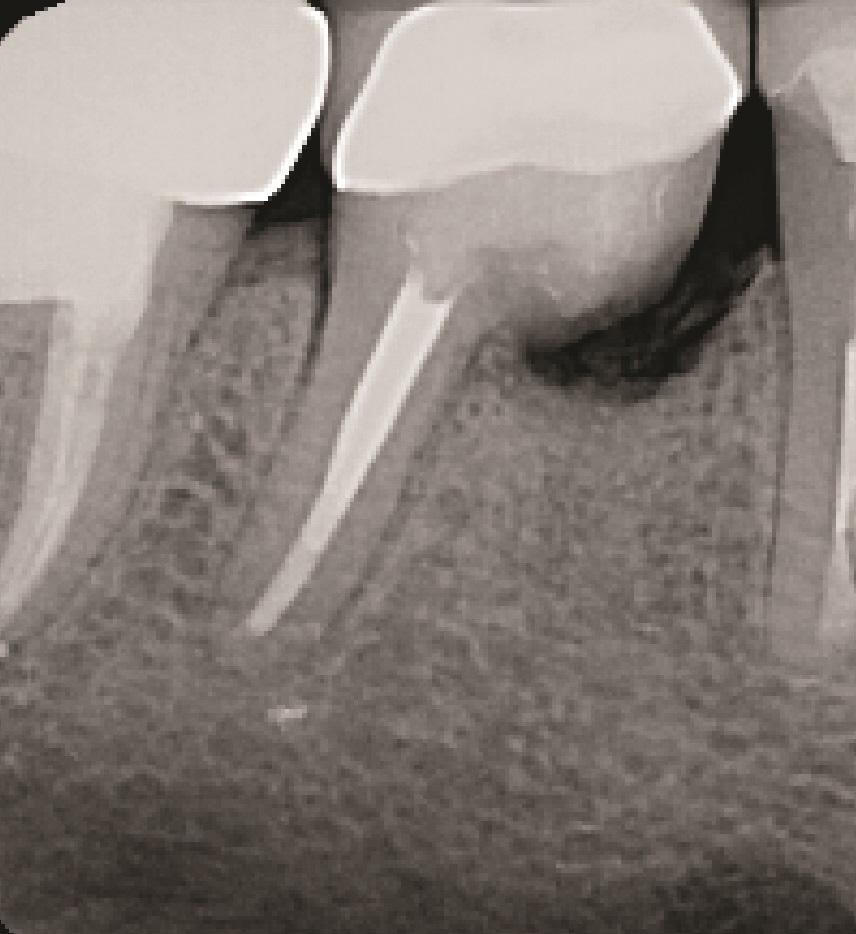

К таким патологическим состояниям относятся вертикальные переломы корней, перфорации корней, пародонтит с поражением корней из-за проблем в области фуркации или сближения корней, сочетанные эндодонтическо-пародонтальные дефекты на фоне коротких корней, устойчивые фуркационные дефекты, значительные не поддающиеся лечению внешние резорбтивные дефекты и другие (Фото 1–4). Когда подобные состояния затрагивают однокорневые зубы, удаление часто является единственным способом устранения патологии. Однако в случае многокорневых зубов существует дополнительная возможность: полное удаление источника патологии с одновременным сохранением функциональности зуба, что демонстрирует опубликованные показатели выживаемости на уровне 80–90%. При правильном выполнении с учетом описанных в статье факторов такое функциональное состояние может сохраняться в долгосрочной перспективе со средним сроком службы от 6 до 20 лет.

Фото 2: Зуб 4.6 с ранее проведенным апикальным хирургическим вмешательством, показывающий потерю кости вокруг переломанного мезиального корня.

Фото 3: Зуб 3.6 с латеральной и апикальной потерей кости в области переломанного мезиального корня.